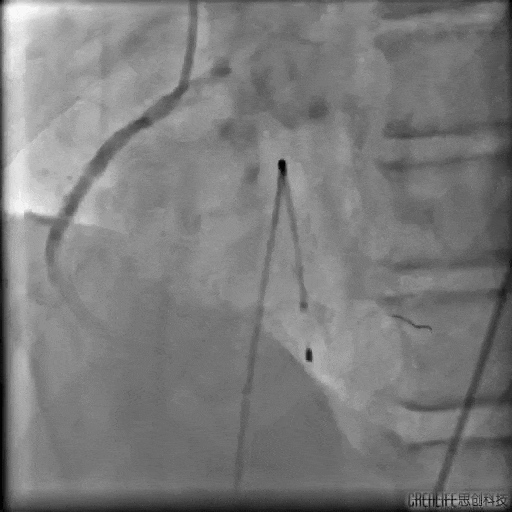

治疗前 宫兆滨主任指挥手术团队,迅速为张先生安装临时起搏器。随着起搏器开始工作,患者血压持续攀升到正常值,心率也从危险的30次/分稳步提升至80次/分,手术条件终于具备!随后,手术团队精准操作,成功打通了张先生阻塞的血管。整个过程历时约40分钟,这场急诊心血管介入手术宣告成功!